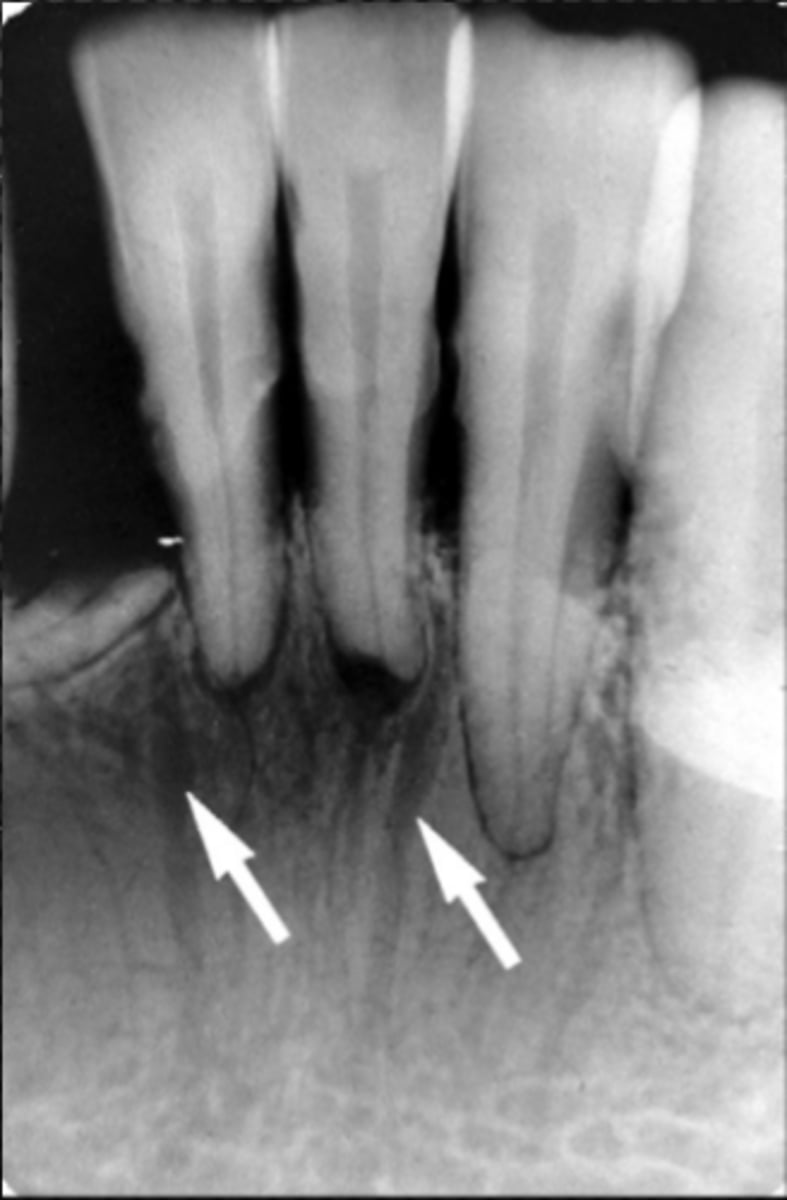

Mental ridge

Identify the radiopaque structure

<p>Identify the radiopaque structure</p>

External oblique ridge

Identify the structure

<p>Identify the structure</p>

Mylohyoid (internal oblique) ridge

Submandibular fossa

Identify the large radiolucent area

<p>Identify the large radiolucent area</p>

inferior boarder of the mandible

anterior border of the ramus

Name the structure the white arrow is pointing to.

<p>Name the structure the white arrow is pointing to.</p>

internal oblique ridge or mylohyoid ridge

Name structure the black arrow is pointing to.

<p>Name structure the black arrow is pointing to.</p>

Name the radiolucent area indicated by the arrows

<p>Name the radiolucent area indicated by the arrows</p>

Genial tubercles (mental spine)

What is creating the radiopaque objects indicated by the arrows?

<p>What is creating the radiopaque objects indicated by the arrows?</p>

What is indicated by the dotted line?

<p>What is indicated by the dotted line?</p>

What makes the inverted-V shaped line indicated?

<p>What makes the inverted-V shaped line indicated?</p>